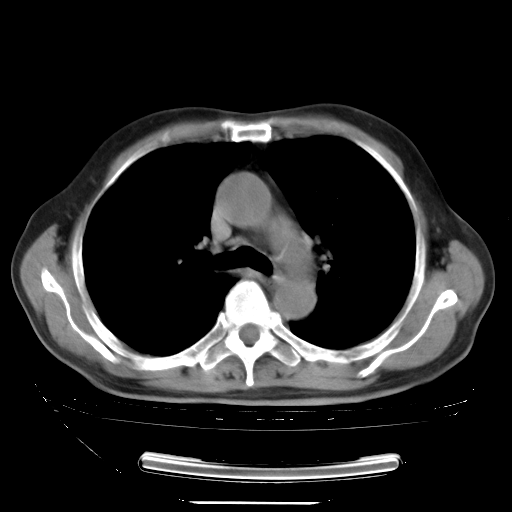

今天复查肺部CT,发现双肺广泛磨玻璃样改变。所以我把3月19日和5月9日相隔50天的肺部CT上传。请大家会诊。

2009年3月19日肺部CT片。

2009年3月19日肺部CT

大致读了系列胸部CT:纵隔窗无明显异常,肺窗:从4、27至今:主要是双肺中下野外带可见毛玻璃样改变,目前处于急性肺泡炎阶段,至于原因考虑1、结替组织或胶原血管性疾病所致?2、恶性疾病如恶组在肺部所致的表现或细支气管肺泡癌?3、药物或其它原因如肺蛋白沉着症所致肺泡炎目前不太可能?总之,明天就去请我院的呼吸科、感染科、血液科和临免专家会诊哈。